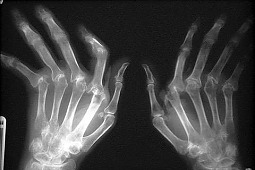

Około 40% ludzi dotkniętych jest chorobą zwyrodnieniową stawów, przynajmniej jednej ręki.

Okazało się, że kobiety były bardziej narażone na chorobę zwyrodnieniową stawów, występowała ona u 47, 2% kobiet i 24,6% mężczyzn. Dolegliwość ta jest częstsza wśród białej populacji – 41,4%, niż wśród czarnej – 29,2%. Większe ryzyko choroby zwyrodnieniowej stawów wiązał się także z nadwagą – 47,1%, w porównaniu do 36,1% występowania u osób bez nadwagi.